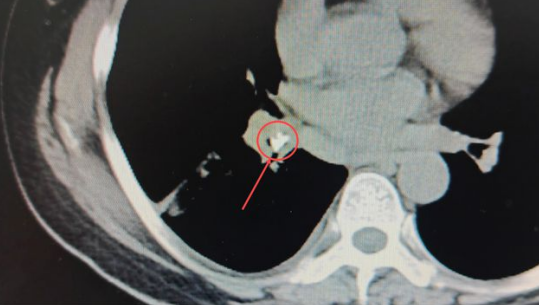

在CT影像中能夠很清晰地發(fā)現(xiàn):患者右肺葉已經(jīng)出現(xiàn)大面積實(shí)變[1],形成“白肺”(正常的肺葉組織在CT影像中呈黑色),在右肺基底段的一截支氣管中,有一個(gè)類似鈣化的“亮點(diǎn)”。醫(yī)生們進(jìn)一步仔細(xì)查看,發(fā)現(xiàn)這個(gè)亮度極高的異物顯示出的密度與骨骼的密度相近。

安女士肺部CT影像中極不尋常的“亮點(diǎn)”,馬上成為醫(yī)生們高度關(guān)注的疑點(diǎn),這也進(jìn)一步印證了礦總呼吸科專家做出的推斷:果然有異常的東西滯留肺內(nèi),才導(dǎo)致患者如此嚴(yán)重的咳喘癥狀。

▼紅圈內(nèi)即卡在肺內(nèi)的異物

孟醫(yī)生說(shuō):“病人原本的右肺有三葉,從CT中能明顯看出其中一葉完全實(shí)變,張不開。如此大面積的肺實(shí)變?nèi)绻荒芗皶r(shí)疏通,很可能導(dǎo)致后期肺器官的萎縮,整個(gè)肺下葉都會(huì)跟著喪失呼吸功能的?!?/p>